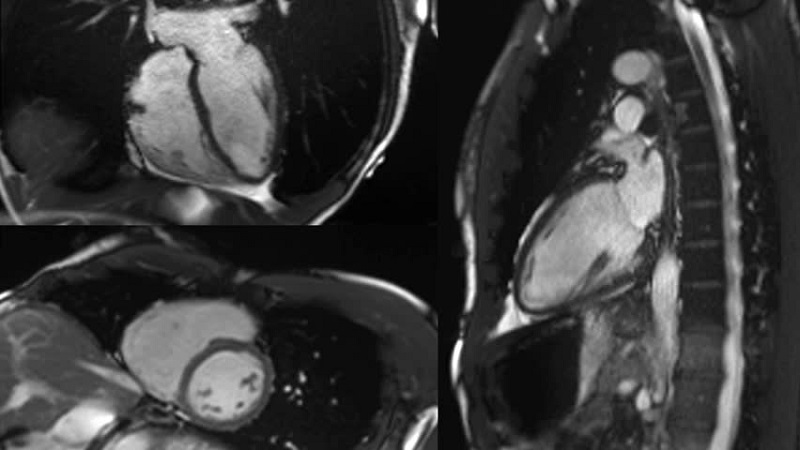

Hiện nay, tại Bệnh viện Thống Nhất (TPHCM) có triển khai dịch vụ chụp cộng hưởng từ tim (MRI tim 1.5 Tesla) với mức chi phí như sau: